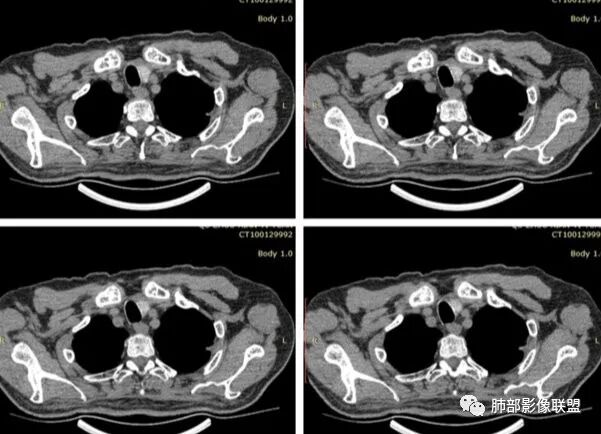

有栽赃吗?

这种属于宽基底与胸膜相连,附近胸膜增厚

栽赃是局部外侵犯

这里没有栽赃

如下图病例红色箭头的是典型栽赃:

南边 :

而该病例栽赃不明显,与增厚的胸膜分界比较清晰

下面这个病例这也是栽赃